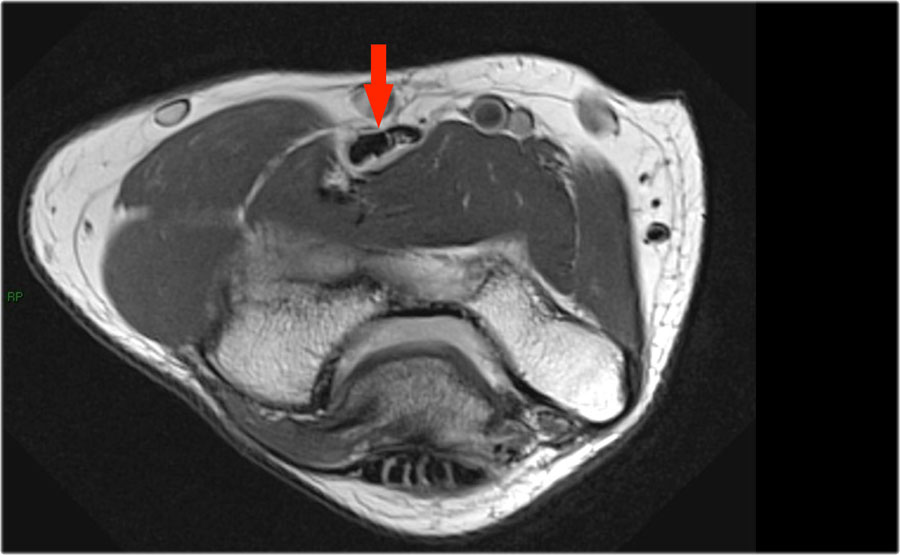

Những hình ảnh này của một nam giới 23 tuổi bị ngã chống tay khi đang trượt ván hai tuần trước.

Khi khám lâm sàng, ghi nhận giảm biên độ vận động khớp khuỷu và đau khi ấn dọc theo mặt ngoài.

Cấu trúc nào nằm phía sau chỏm quay trên hình ảnh cắt ngang?

Sagittal view:

- Một lần nữa, hình ảnh đặc trưng của phù tủy xương thường gặp trong trật khớp khuỷu tay ra sau với vết dập ở phía trước của chỏm xương quay (mũi tên đỏ) và ở phía sau của chỏm con xương cánh tay.

- Chỏm quay phải đã va chạm vào phần sau của chỏm con xương cánh tay.

Cấu trúc phía sau chỏm quay là dây chằng vòng.

Nó không đều và dày lên do hậu quả của trật khớp ra sau.